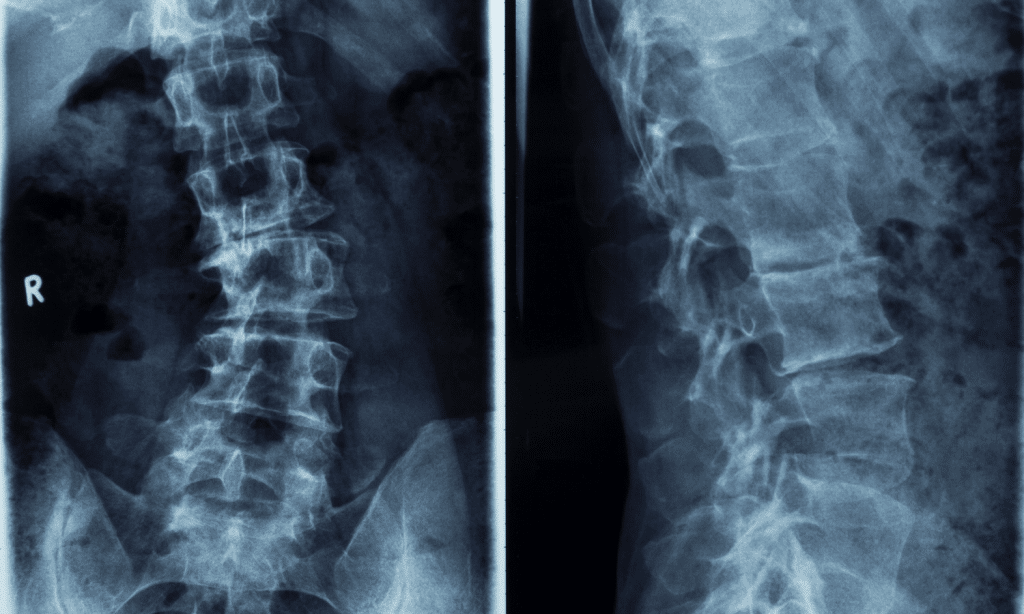

We always hear about it, but what is the working definition of scoliosis? According to the Cleveland Clinic, it is simply defined as an abnormal curvature of our spine, and has different types based on where the curve is, how bad it is and what caused it. For some sources the curve in the spine has to be measured as 10 degrees or greater (called “The Cobb Angle”) to truly be considered scoliosis.